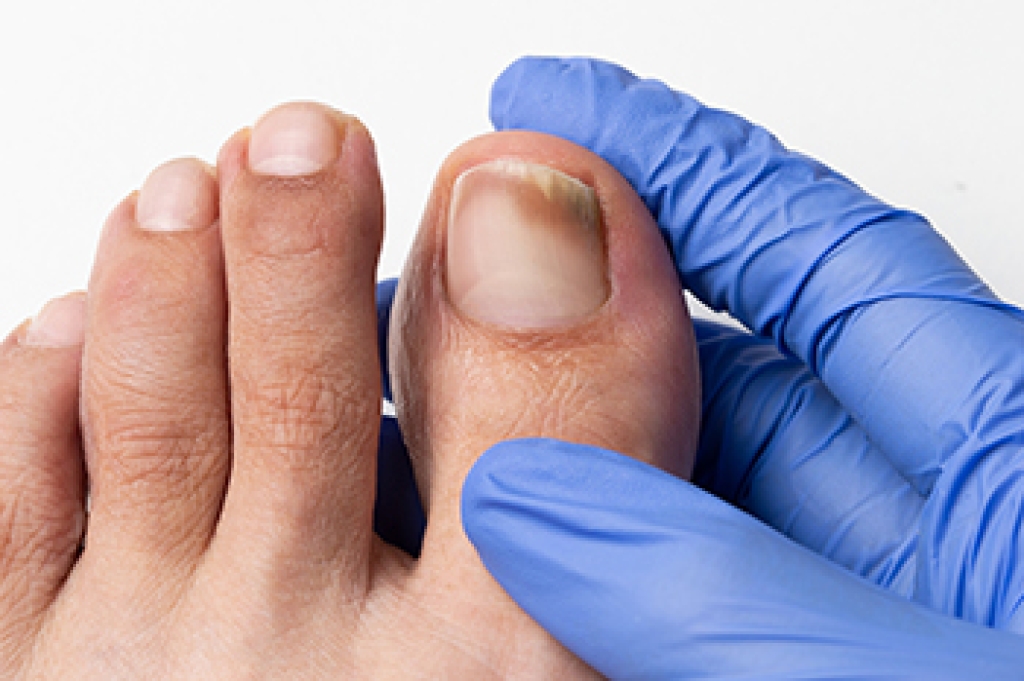

Toenail fungus can cause the toenails to become brittle and yellow. They can gradually harden and become thicker, causing difficulty in having them properly trimmed. This unsightly foot condition is caused by a fungal infection, and is considered to be contagious. This type of fungus lives and thrives in warm and moist environments, consisting of shower room floors, public swimming pools, and similar areas. The fungus can enter the body through tiny cracks in the skin, and it is beneficial to wear appropriate shoes while in these types of areas. A diagnosis is performed by extracting a small sample of the nail. After confirmation is received, treatment can begin. There are various methods that can accomplish this, and it is strongly suggested a podiatrist is contacted as quickly as possible who can prescribe proper medication.

If left untreated, toenail fungus may spread to other toenails, skin, or even fingernails. If you suspect you have toenail fungus it is important to seek treatment right away. For more information about treatment, contact Cary Golub, DPM of New York. Our doctor can provide the care you need to keep you pain-free and on your feet.

Symptoms

- Warped or oddly shaped nails

- Yellowish nails

- Loose/separated nail

- Buildup of bits and pieces of nail fragments under the nail

- Brittle, broken, thickened nail

If self-care strategies and over-the-counter medications does not help your fungus, your podiatrist may give you a prescription drug instead. Even if you find relief from your toenail fungus symptoms, you may experience a repeat infection in the future.